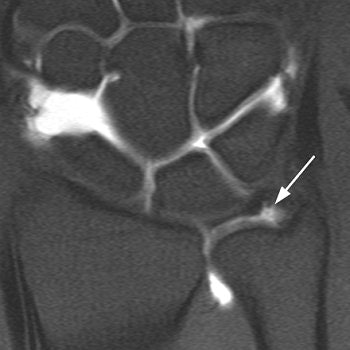

![]() |

| Same patient as above. Conventional arthrogram of distal radioulnar joint shows contrast agent pooling in triangular fibrocartilage defect (arrowheads). Rüegger C, Schmid MR, Pfirrmann CWA, Nagy L, Gilula LA, and Zanetti M. "Peripheral Tear of the Triangular Fibrocartilage: Depiction with MR Arthrography of the Distal Radioulnar Joint" (AJR 2007; 188:187-192). |